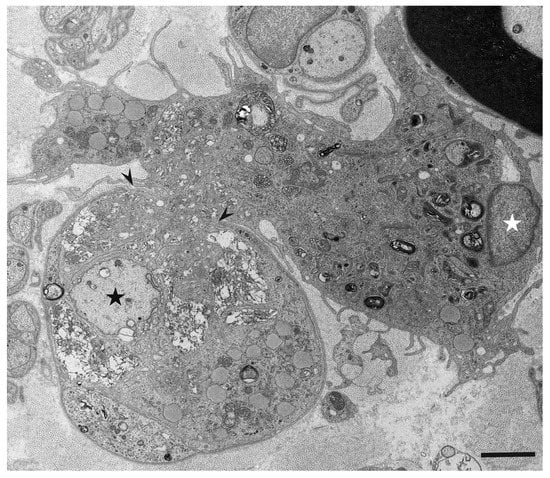

- Koike, H.; Nishi, R.; Ikeda, S.; Kawagashira, Y.; Iijima, M.; Katsuno, M.; Sobue, G. Ultrastructural mechanisms of macrophage-induced demyelination in CIDP. Neurology 2018, 91, 1051–1060. [Google Scholar] [CrossRef]

- Koike, H.; Fukami, Y.; Nishi, R.; Kawagashira, Y.; Iijima, M.; Katsuno, M.; Sobue, G. Ultrastructural mechanisms of macrophage-induced demyelination in Guillain-Barré syndrome. J. Neurol. Neurosurg. Psychiatry 2020, 91, 650–659. [Google Scholar] [CrossRef]

- Koike, H.; Katsuno, M.; Sobue, G. Deciphering the mechanism and spectrum of chronic inflammatory demyelinating polyneuropathy using morphology. Clin. Exp. Neuroimmunol. 2018, 9, 35–46. [Google Scholar] [CrossRef]

- Koike, H.; Katsuno, M. The role of macrophages in Guillain-Barré syndrome and chronic inflammatory demyelinating polyneuropathy. Neurol. Clin. Neurosci 2021, in press. [Google Scholar] [CrossRef]